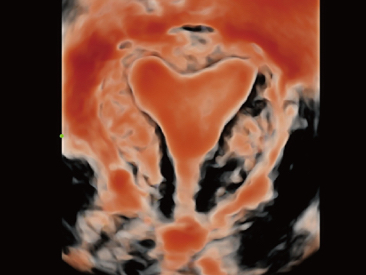

Assim como o n├Łvel de qualidade de imagem premium, o Resona 7 tamb├®m melhora as capacidades de investiga??o cl├Łnica com o revolucion├Īrio Fluxo V para avalia??o hemodin?mica vascular e a aquisi??o de plano mais inteligente do conjunto de dados 3D para diagn├│stico CNS fetal. Combinando a opera??o mais intuitiva baseada em gesto de multi-toques e todos os recursos cl├Łnicos essenciais, Resona 7 est├Ī realmente conduzindo novas ondas na inova??o de ultra-som.